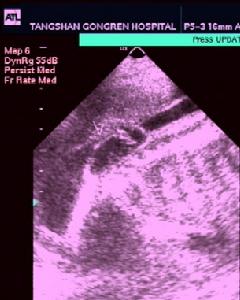

脊柱裂脊柱裂的發病機理有兩種假說:其一認為整個畸形是由於胚胎期原發性水動力學紊亂所致;其二認為病因是胚胎髮育時期神經管閉合的失敗。後一種假說已得到廣泛的承認。脊柱裂的產前診斷尚較困難。在有嚴重神經管缺陷胎兒的妊娠婦女血清中或羊水中甲胎蛋白 (α-胎蛋白)常異常增高。B型超音波檢查亦有助於診斷。